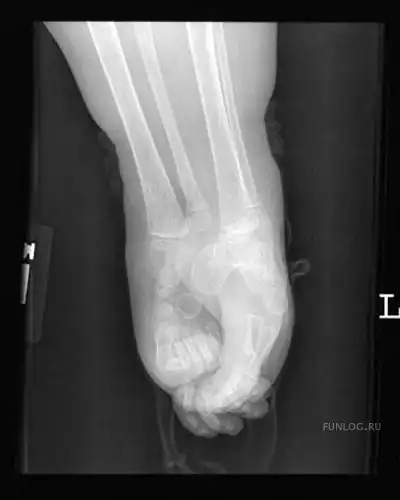

Большинство детей с «сиреномелией» - редким врожденным пороком развития – так называемым «синдромом русалки» погибают в первые часы после появления на свет из-за многочисленных сопутствующих дефектов развития…В настоящее время в мире известны три случая спасения детей с подобным синдромом – это американка Тифани Йоркс, успешно перенесшая операцию по разделению ног 19 лет назад,трехлетняя перуанская девочка Милагрос Серрон, последняя операция по разделению ног которой была проведена летом этого года, и Шилох Пепин, единственная, кого так и не прооперировали…

Кроме сросшихся ног у девочки при рождении не досчитались мочевого пузыря, матки, толстого кишечника, влагалища…У неё была лишь одна недоразвитая почка и один яичник…

Серьезной проблемой было отсутствие так называемых вертлюжных впадин - суставных ямок для бедер - без них девочка не смогла бы стоять. Однако выяснилось, что постепенно ее скелет сформировал нужные части…